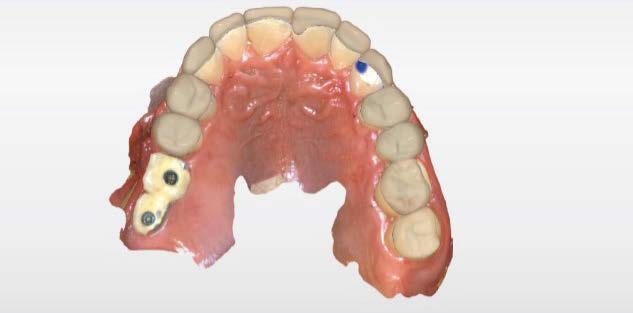

dentarias, cumpliendo parámetros biológicos, terapéuticos, mecánicos y estéticos. Después se realizó un modelado digital retrospectivo (Figuras 7-11) para generar modelos impresos 3D para realizar el mock up funcional, estético y como guía para las preparaciones (Figuras 12-15). Con ello, se efectuaron las preparaciones dentarias y los registros intermaxilares y, posteriormente, se digitalizaron ambos maxilares (Figuras 16-21)

Terminada esta fase se elaboró una propuesta de diseño (CEREC,

SW 5.2, Dentsply Sirona) (Figuras 22-27), la cual fue materializada en dos tipos de materiales a partir de bloques cerámicos IPS Empress CAD y cerámica vítrea de disilicato de litio IPS E.max CAD (Figuras 28-30)

Figura 7. Modelado digital. Figura 9. Propuesta de diseño en oclusión Figura 10. Vista lateral derecha. Figura 8. Propuesta de diseño arcada superior. Figura 11. Vista oclusal superior del modelado. Figura 12. Mock Up impreso en oclusión. Figura 14. Mock Up que evidencia el desgaste dentario en el maxilar inferior.

Figura 17. Digitalización maxilar superior e inferior. Figura 18. Digitalización maxilar inferior. Figura 15. Mock Up completo los dientes inferiores Figura 16. Preparaciones y registros interoclusales. Figura 19. Vista lateral, modelo digital inferior. Figura 20. Vista oclusal, modelo digital inferior.

Figura 25. Vista oclusal del diseño de las restauraciones en maxilar inferior. Figura 24. Diseño digital de las restauraciones maxilar inferior, vista frontal. Figura 21. Uso del Mock up para la determinación del registro intermaxilar. Figura 23. Diseño en oclusión, vista lateral. Figura 22. Diseño en oclusión. Vista frontal. Figura 26. Diseño digital de las restauraciones.